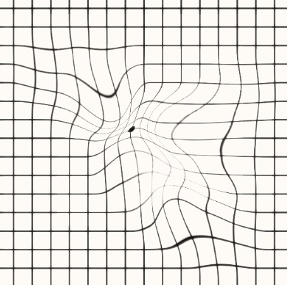

2. 시야 왜곡 (Visual Distortion)

- 시야의 중앙부에서 왜곡된 이미지가 나타날 수 있습니다. 직선이 구부러져 보이거나, 물체가 비정상적으로 확대되어 보이는 현상이 발생합니다.

- 예를 들어, 문자나 얼굴이 왜곡되어 나타나거나, 모양이 부풀어 오르거나 찌그러진 것처럼 보일 수 있습니다.

- 이러한 왜곡은 시각적 경험에 큰 영향을 미쳐 일상적인 활동(예: 읽기, 운전, 얼굴 인식)에 어려움을 겪게 합니다.